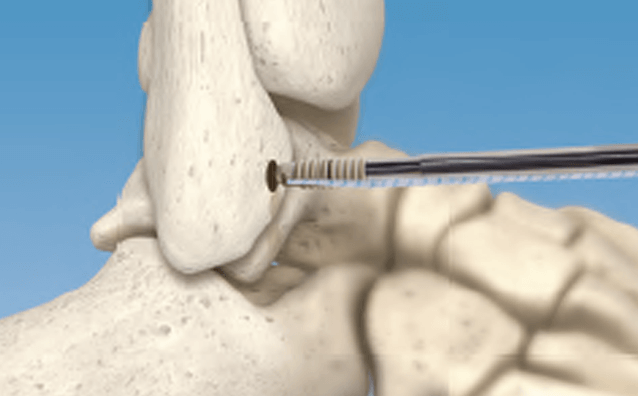

Arthroscopic Talus OCD Repair with CartiMax® Viable Cartilage Allograft - Dustin D. Constant, DPM